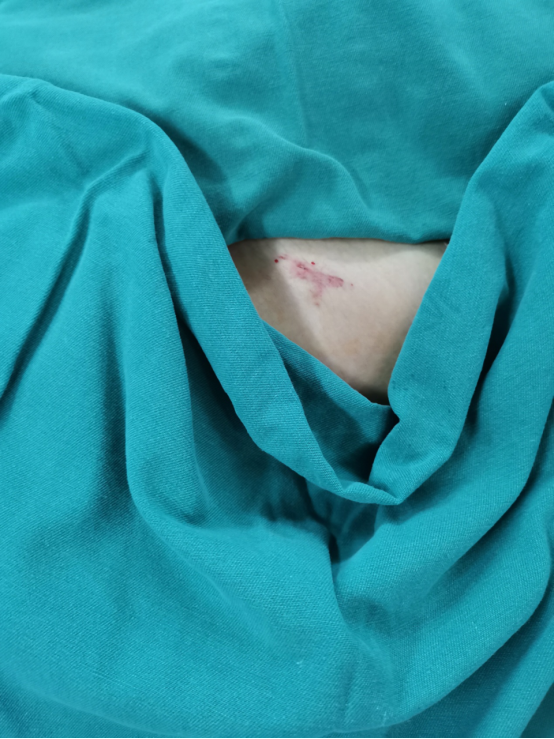

由于在传统手术方式中,为确保骨折固定置入螺钉位置的准确性,往往需要作大切口,术中医生还需要反复透视定位查看置钉位置,不仅创伤大、时间长,X线辐射暴露次数也很多。因此,团队为菲菲制定了微创手术方案,术中团队精准定位、精细操作,手术切口仅2厘米,出血不到10ml,一期为菲菲完成了左侧骨盆骨折内固定手术,术后恢复顺利。

▲微创切口仅2㎝

▲传统切口大、出血多